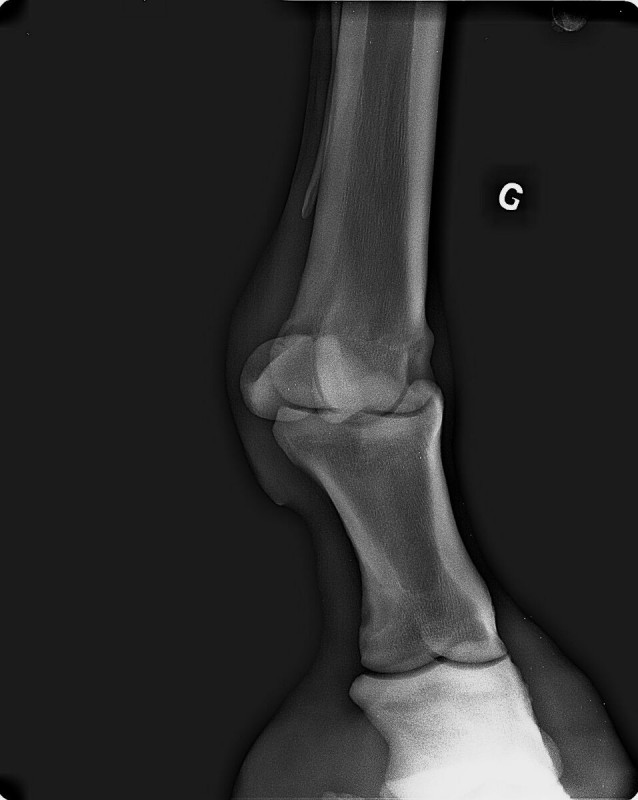

Radios que voici (on "voit" la boule, à gauche sur la deuxième radio et à droite sur la troisième) :